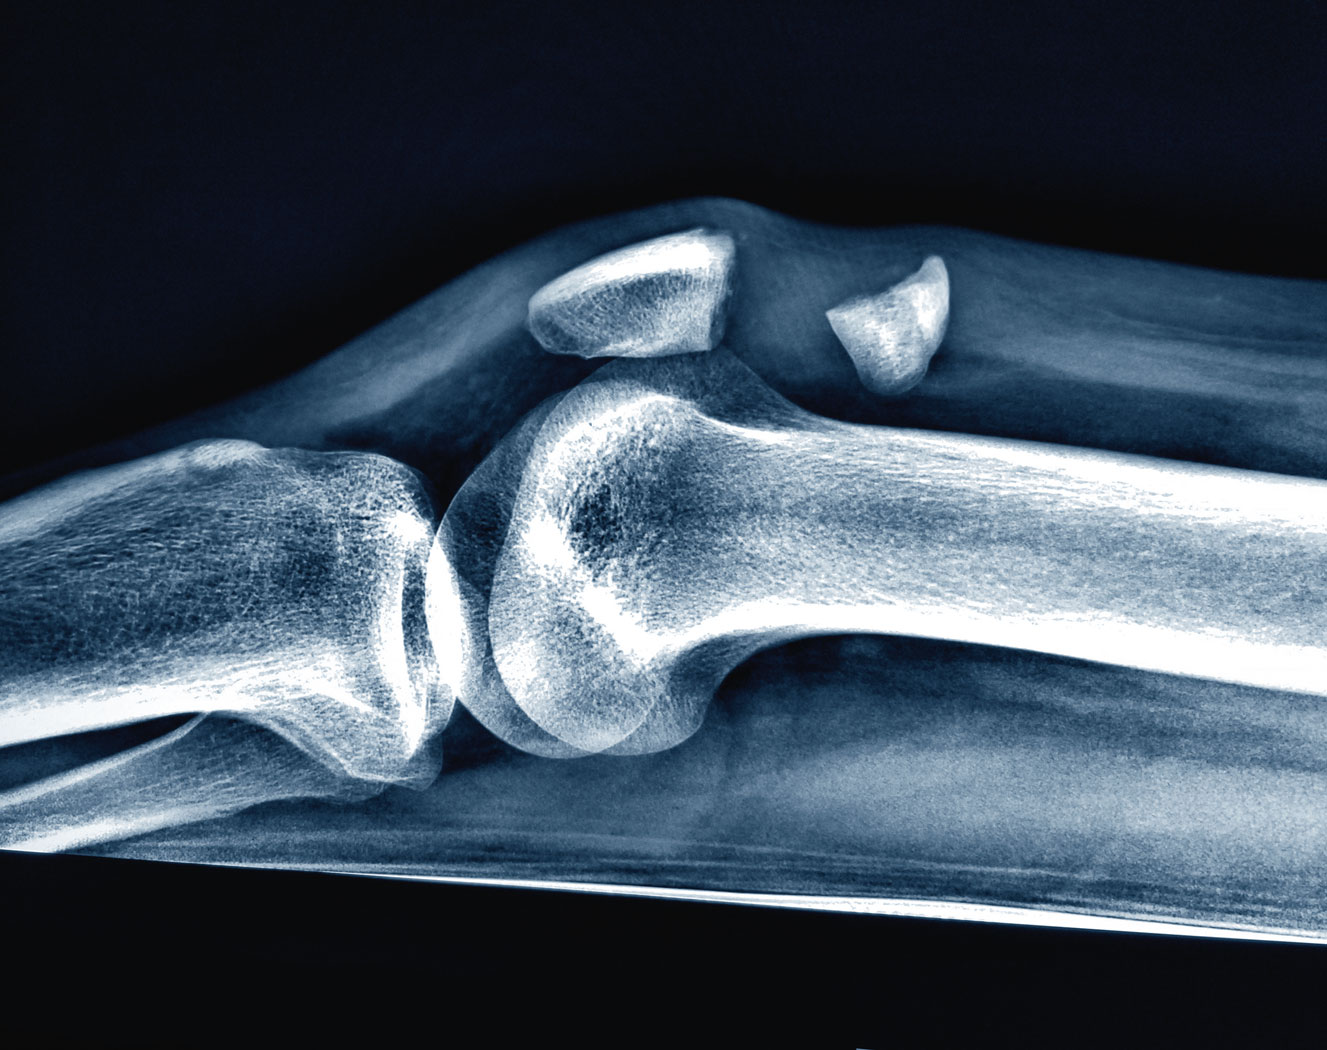

Złamanie kości rzepki. Złamanie kości rzepki. materiały prasowe